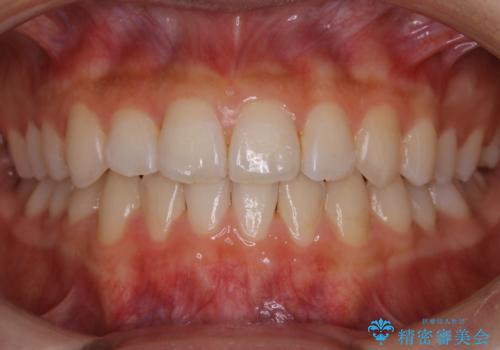

【非抜歯】受け口の改善 10代で始める本格的噛み合わせ治療

- 受け口の改善と前歯のガタつきの治療を主訴にご来院されました。

こちらの患者様の場合、上の前歯のガタつきが原因で口を閉じる際に上下の前歯の先端同士が先に当たってしまい、そこからさらに深く噛み込もうとすると下顎が前にずれていってしまうという、機能性の反対咬合であることが検査の結果わかりました。

そのため、まずは上顎の前歯のガタつきを改善していき、前歯が先に当たってしまうという症状を改善し噛み込む位置を後方の本来の位置に誘導する方法をとりました。

本来、正常な噛み合わせの場合は上顎の前歯が下顎の前歯より前に覆いかぶさるように噛み込んでくる状態が理想的です。

それに対して「反対咬合(受け口)」の場合は、下顎の前歯が上顎の前歯より前に出てきてしまう状態を指します。